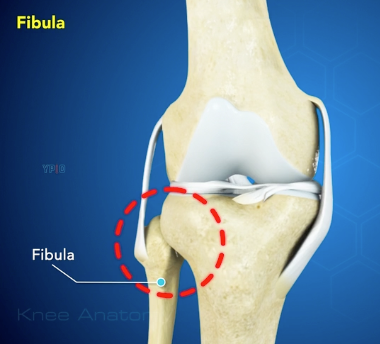

Szárkapocscsont (fibula):

A szárkapocscsont, bár nem teherviselő csont fontos szerepe van a térd oldal szalagok (MCL, LCL) és a bicepsz femoris ín tapadásában.